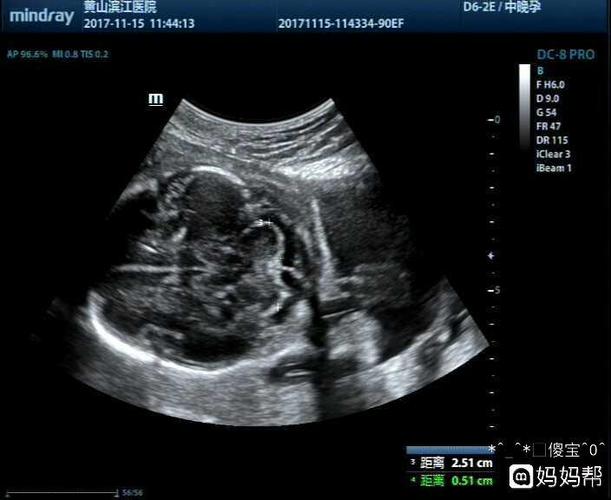

女宝的四维图器官,四个月女宝器官b超图

发个四维让你们帮我看看男宝女宝